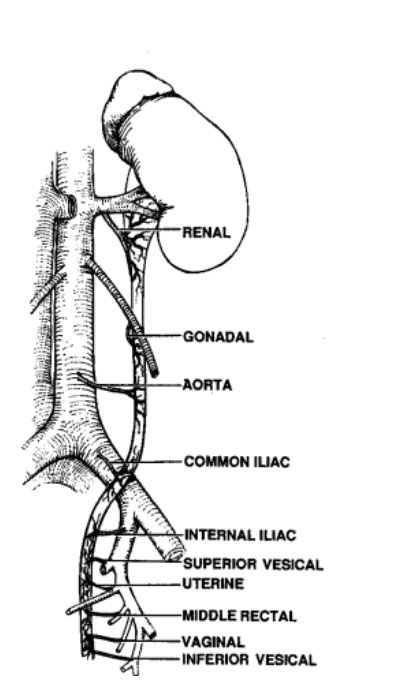

如下图所示,沿输尿管走行,其接受多支动脉血供(如下图所示),在腹膜后,依次为肾动脉、生殖动脉、腹主动脉和髂总动脉。进入盆腔后,远端输尿管的血液供应包括髂内动脉或其分支,尤其是膀胱和子宫动脉,还有直肠中动脉和阴道动脉等。这些分支到达输尿管后,分布在筋膜层并上下沟通,形成动脉网,然后再散布到其他各层。因输尿管的血供具有广泛的交通支,所以可以安全的适当范围游离输尿管而不会导致输尿管坏死。

The sources of arterial blood supply to the ureter